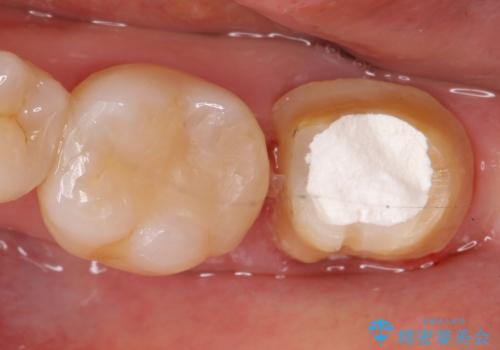

- 他院にて根管治療を行っていたが、痛みが引かないため当院での診療を希望された方の症例です。

改めて再根管治療を行い、症状の緩解を確認後、オールセラミッククラウンによる補綴を行いました。